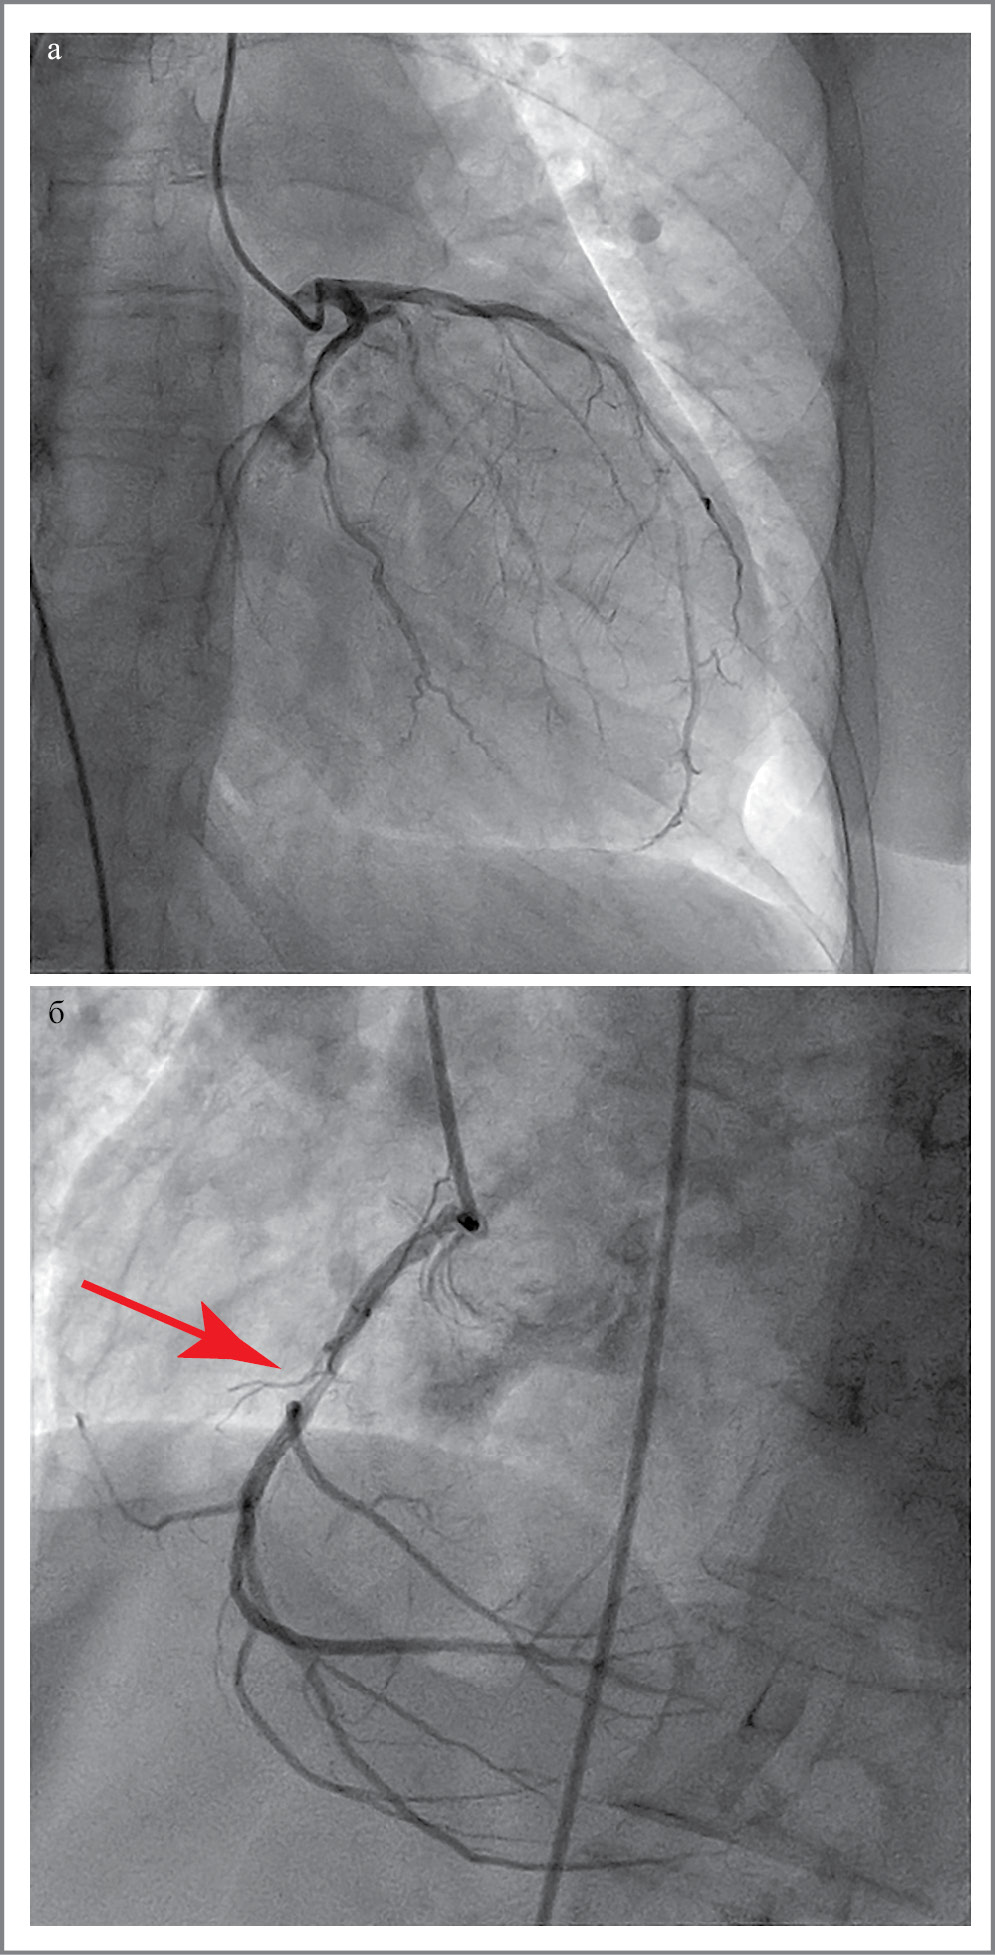

Коронароангиография: правый тип коронарного кровоснабжения. Стеноз до 70% в средней трети правой коронарной артерии. Левая коронарная артерия без значимых стенозов (рис. 4).

Рис. 4. Коронарограмма: а – левая коронарная артерия; б – правая коронарная артерия (стрелкой обозначен стеноз правой коронарной артерии).

Fig. 4. Coronary angiogram: a – left coronary artery; b – right coronary artery (arrow indicates stenosis of the right coronary artery).